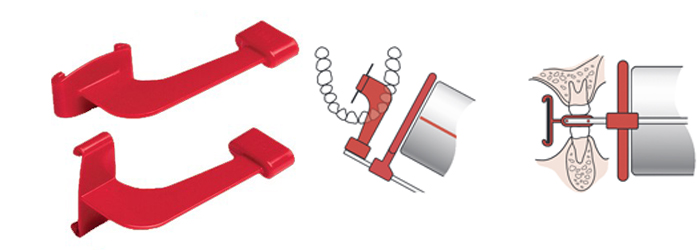

L’utilisation du XCP nécessite un apprentissage simple mais nécessaire. Une petit astuce pour savoir s’il a été monté à l’envers est que le film doit toujours être centré à travers le cercle et que la fixation du film doit arriver à la fin pour être dans le visage interne ou lingual du patient.

Pour réaliser des radiographies périapicales antérieures (XCP Bleu) dans chaque arcade, il suffit de les tourner vers le haut ou le bas . Mais pour la réalisation de radiographies périapicales postérieures (XCP Jaune XCP), l’assemblage peut être plus compliqué et en dehors de la perte de temps, il peu occasionné un inconfort et un manque de professionnalisme en face des clients de votre cabinet dentaire.